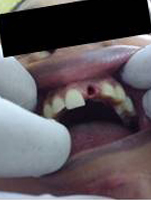

Pre Operation

Single Tooth Implant

Punch Cut

Placement of Bone Grafting

After Punch Cut